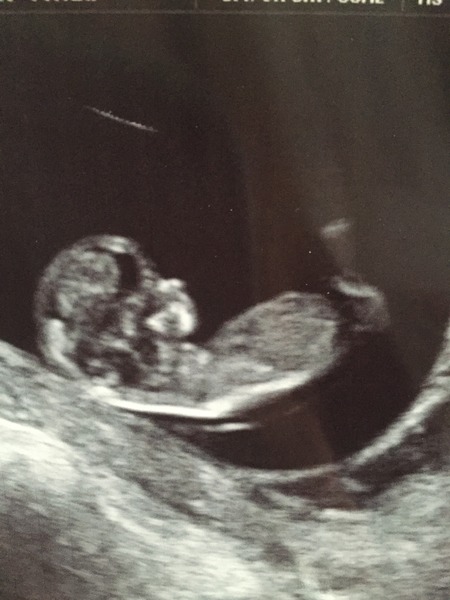

I had my first scan this morning and I feel like a new woman! All my fears have been wiped away and just so so happy. Could see the baby moving around and such a strong heartbeat. DH looks completely shell shocked though, think it is only now starting to sink in!

PS they dated me at 11+1 which is just one day off what I thought.

Wow peamad, it really looks like a baby! So exciting and I'm so pleased for you. Wonderful to have some of the stress relieved!

How lovely peamad, congratulations! Your baby looks like (s)he's smiling! Smile

pea congrats on your scan, brilliant picture, so clear! It's hard to believe just a few short weeks ago they all looked like little prawns and blobs, and now they're proper little babies!

Yes pea congrats on your scan, just seen your pic...amazing! such a cute little nose Grin